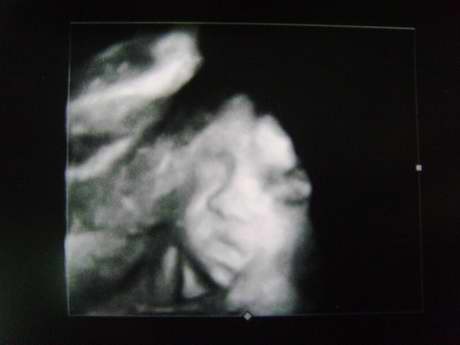

[4D超音波]

婦產科送了兩次4D的超音波,今天就跟老大還有婆婆一起去照~

不過小菜包一點也不賞臉,把臉塞在子宮壁跟胎盤中間,

手還不時的擋著....照了很久才找到稍微清楚的輪廓...

左邊擋住臉頰的是胎盤,右邊則是子宮壁。

超音波室的小姐說鼻子比較像我哩......^^

*小菜包吐舌頭

*打哈欠

*可愛的腳丫子